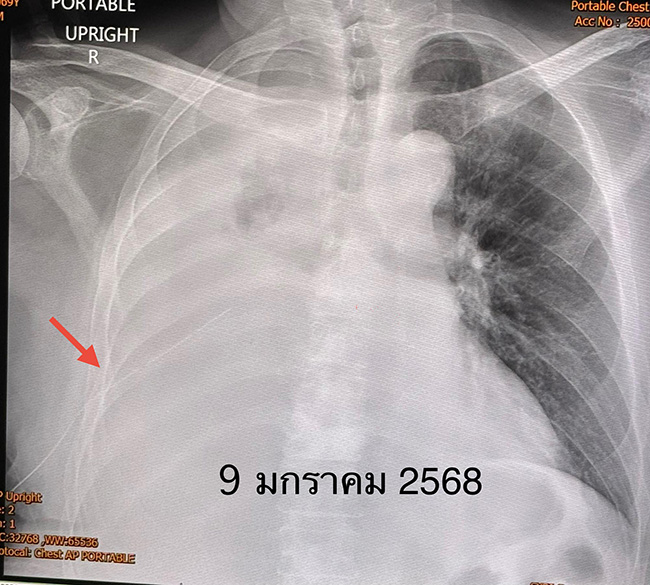

เดือนธันวาคม 2567 เริ่มเหนื่อย มะเร็งกระจายเข้าเยื่อหุ้มปอดข้างขวา ทำให้เกิดน้ำในช่องเยื่อหุ้มปอดข้างขวา ต้องเจาะระบายน้ำ 3 ครั้ง แต่น้ำก็กลับมาอีก เอกซเรย์ปอดข้างขวาขาวทั้งข้าง เข้านอนโรงพยาบาลเพื่อใส่ท่อระบายน้ำจากช่องเยื่อหุ้มปอดด้านขวา และฉีดแป้ง talc ซึ่งประกอบด้วย magnesium silicate ผสมน้ำเกลือเข้าในโพรงเยื่อหุ้มปอด (talc pleurodesis)

หลังฉีดแป้ง ไม่มีผลข้างเคียง น้ำในช่องเยื่อหุ้มปอดลดลง สามารถถอดท่อระบายน้ำออกภายใน 7 วัน ให้กลับบ้านได้ ผู้ป่วยรายนี้เป็นมะเร็งปอดระยะสุดท้าย ให้ยาลดการปวดและทรมาน